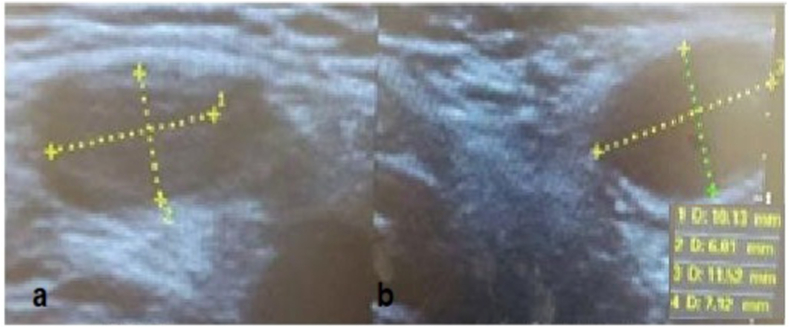

Adhesions and peritoneal attachments were released to gain length and the testis was brought to the neck of the hemiscrotum with slight tension where it was attached. Patient was discharged the following day. Five months after laparoscopic orchiopexy, the testis remains in the neck of the left hemiscrotum with good vascularization but with very small progressive development (10 × 6 millimeters) compared to the contra lateral testis (11.5 × 7.1 mm) (Fig. 3).

Fig. 3.

Ultrasonographic image of the left (a) and the right (b) testis, 5 months after laparoscopic orchiopexy.